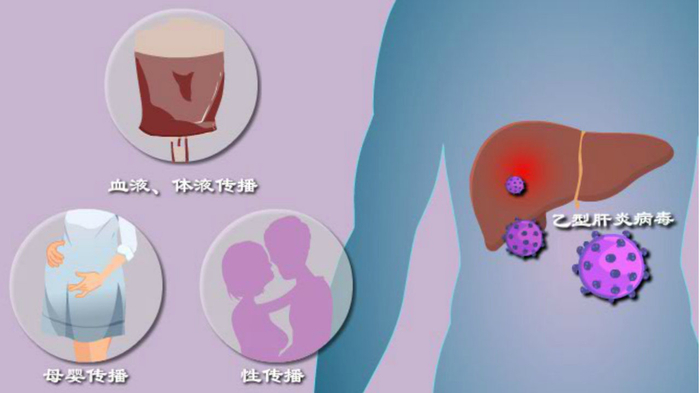

近日,深圳一名孕26周的孕妇在产检一路绿灯的情况下突发高烧入院在入院17个小时后不幸流产(图片来源:视觉中国)短短17小时,女子当晚流产!近日,深圳市第三人民医院急诊科在凌晨接收了处于孕中期的孕妇小陈,她因反复发热被送医。“患者来的时候情况非常紧急,高烧39℃,胎儿心率极快,已经出现不规律宫缩。”小陈的主管医生回忆道。这意味着,随时可能出现流产、死胎、出生缺陷和新生儿死亡等情况。产科医疗团队立即展......

来源:宁波晚报 近日“深圳市第三人民医院”微信公众号发布了一则案例深圳30岁的小陈(化名)在孕26周前产检一路绿灯顺利进入孕中期就在她以为一切都会平稳顺利时意外,却毫无征兆地发生了短短17个小时凌晨入院,当晚流产近日,深圳市第三人民医院急诊科在凌晨接收了一位特殊患者,处于孕中期的小陈因反复发热被送医。“患者来的时候情况非常紧急,高烧39℃,胎儿心率极快,已经出现不规律宫缩。”小陈的主管医生回忆道。......